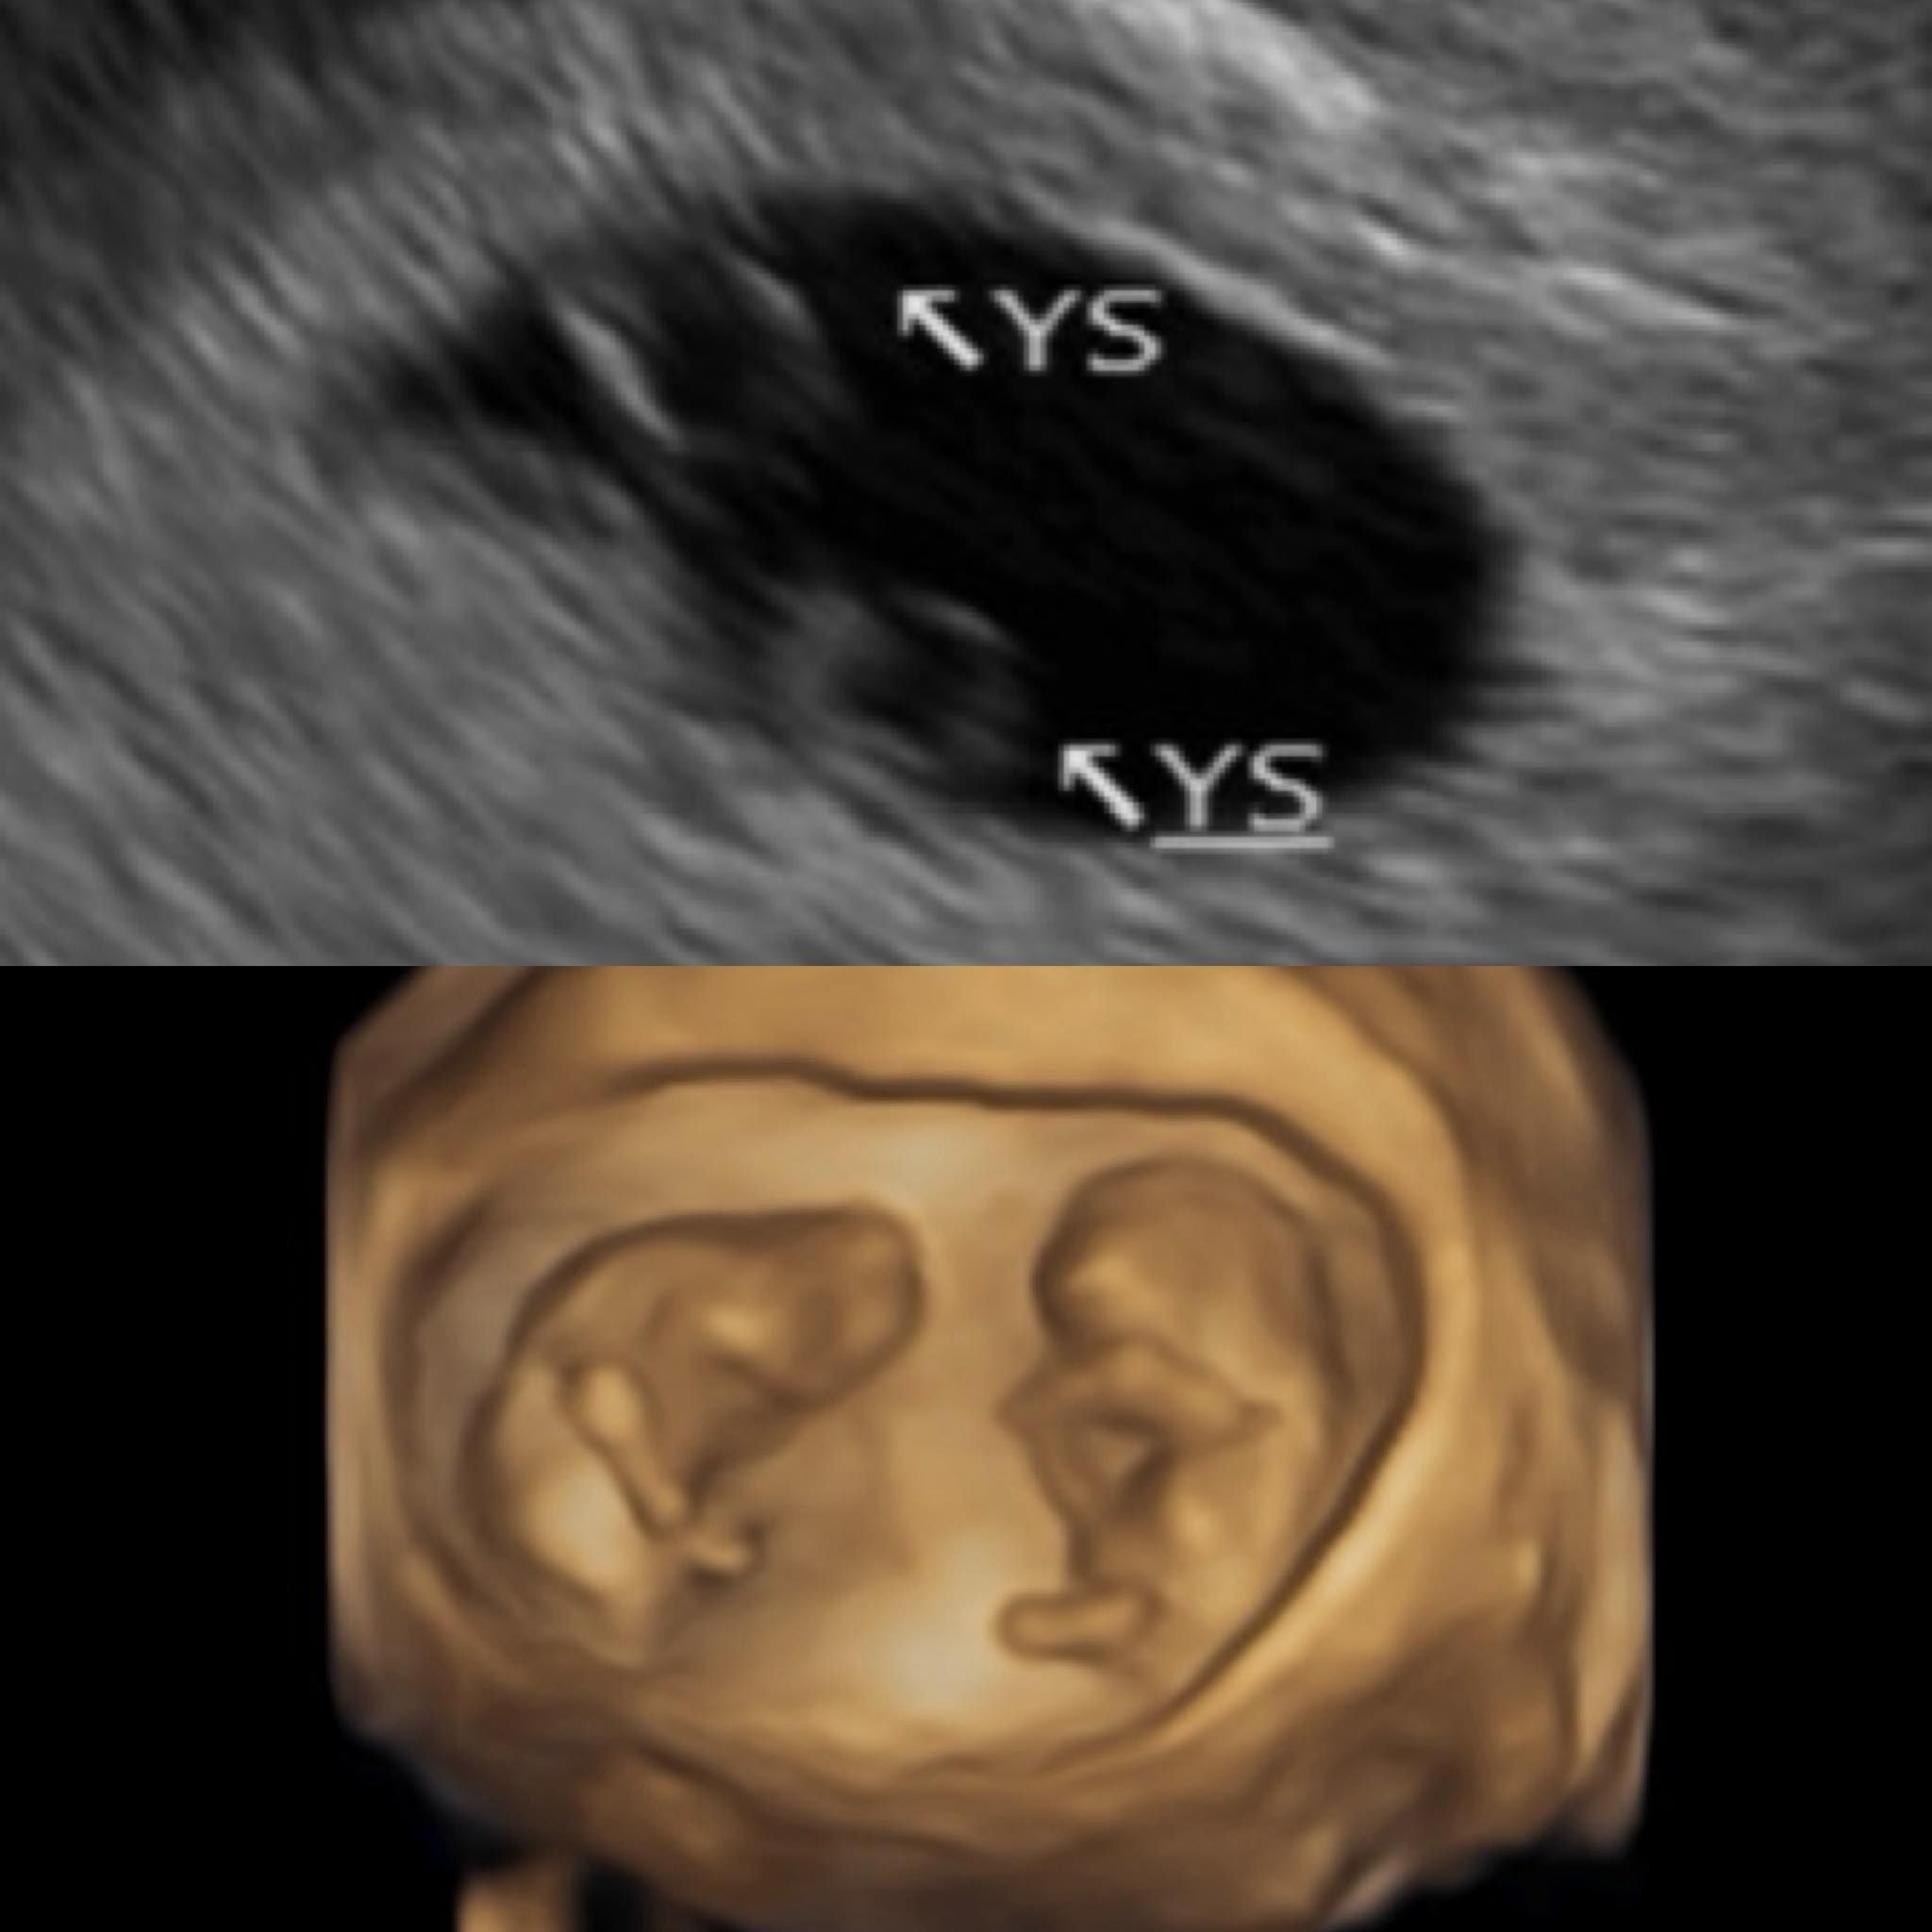

藝人鄭家純(雞排妹)於今日(20日)驚喜宣布懷孕喜訊!與日籍醫生老公 Akira 結婚兩年的她,透露目前已懷胎 12 週,且是珍貴的**「同卵雙胞胎」**。她在社群上分享寶寶 10 週大的超音波照,兩位寶寶一上一下的姿態被她形容「像太極一樣」,畫面既神聖又溫馨。

家純感性分享,上次小產後曾認真向「無緣的小孩」介紹家裡的愛貓阿寶,希望能推薦寶寶回來,沒想到這次「不僅回來了,還多揪了一個手足」。這份意外的驚喜讓她在 6 週大聽到心跳聲的瞬間,忍不住流下感動的淚水。